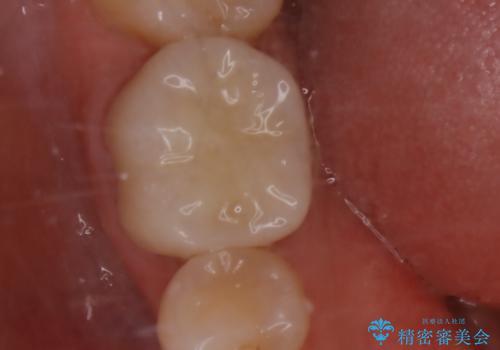

根管治療をした歯は神経のある歯と比較して強度が下がり、長期的に破折のリスクが高まると言われています。破折のリスクを軽減させるため、根管治療を行った歯に対しては歯冠をすべて覆うクラウンという被せ物にて補綴処置を行います。

適合不良の補綴物は二次的な虫歯発生のリスクが高まります。

自費診療で用いられる材料は保険適応の材料に比べて、より精密で適合の良い被せ物作ることができるため、長期的な虫歯のリスクを大幅に減らすことが可能です。